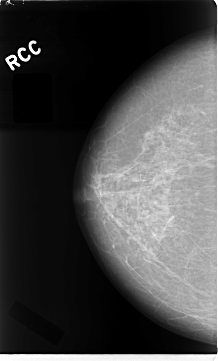

C_0018_1.RIGHT_CC

RIGHT_CC LINES 4688 PIXELS_PER_LINE 2832 BITS_PER_PIXEL 12 RESOLUTION 50 NON_OVERLAY